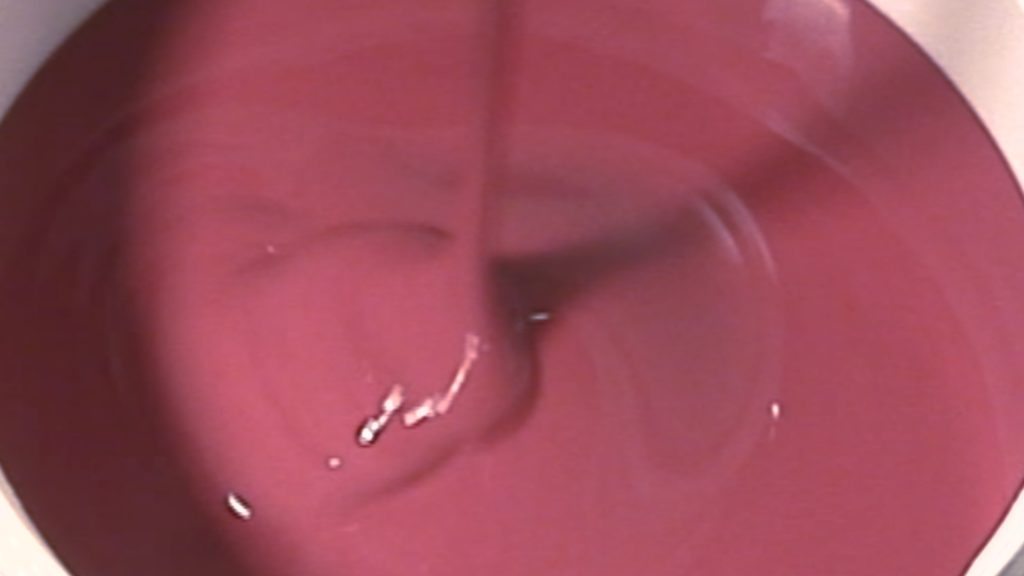

Die erste Schicht Silikon kann nun angerührt werden. Dabei wird das Silikon mit der entsprechenden Menge Vernetzer gemischt. Dieses Verhältnis findet man in der Gebrauchsanleitung. Dann wird die Masse gut verrührt.

Der Aufbau der Gussform erfolgt in 2 Schichten. Zuerst wird eine Schicht bis knapp unter die Oberkante des abzugießenden Objektes aufgefüllt. Wenn diese Ausgehärtet ist, wird nach Auftragen einer Trennschicht eine zweite Schicht aufgegossen. Leichtes Schütteln und Klopfen an der Form beseitigt noch die letzten kleinen Lufteinschlüsse.

Bei einer Glockenform wird das Glas an dem Boden des Gefäßes fixiert und das Silikon über die Form gegossen. Nach der Austrocknung wird die zweite Seite gegossen. Vorher aber mit Silikontrennmittel eingesprüht.